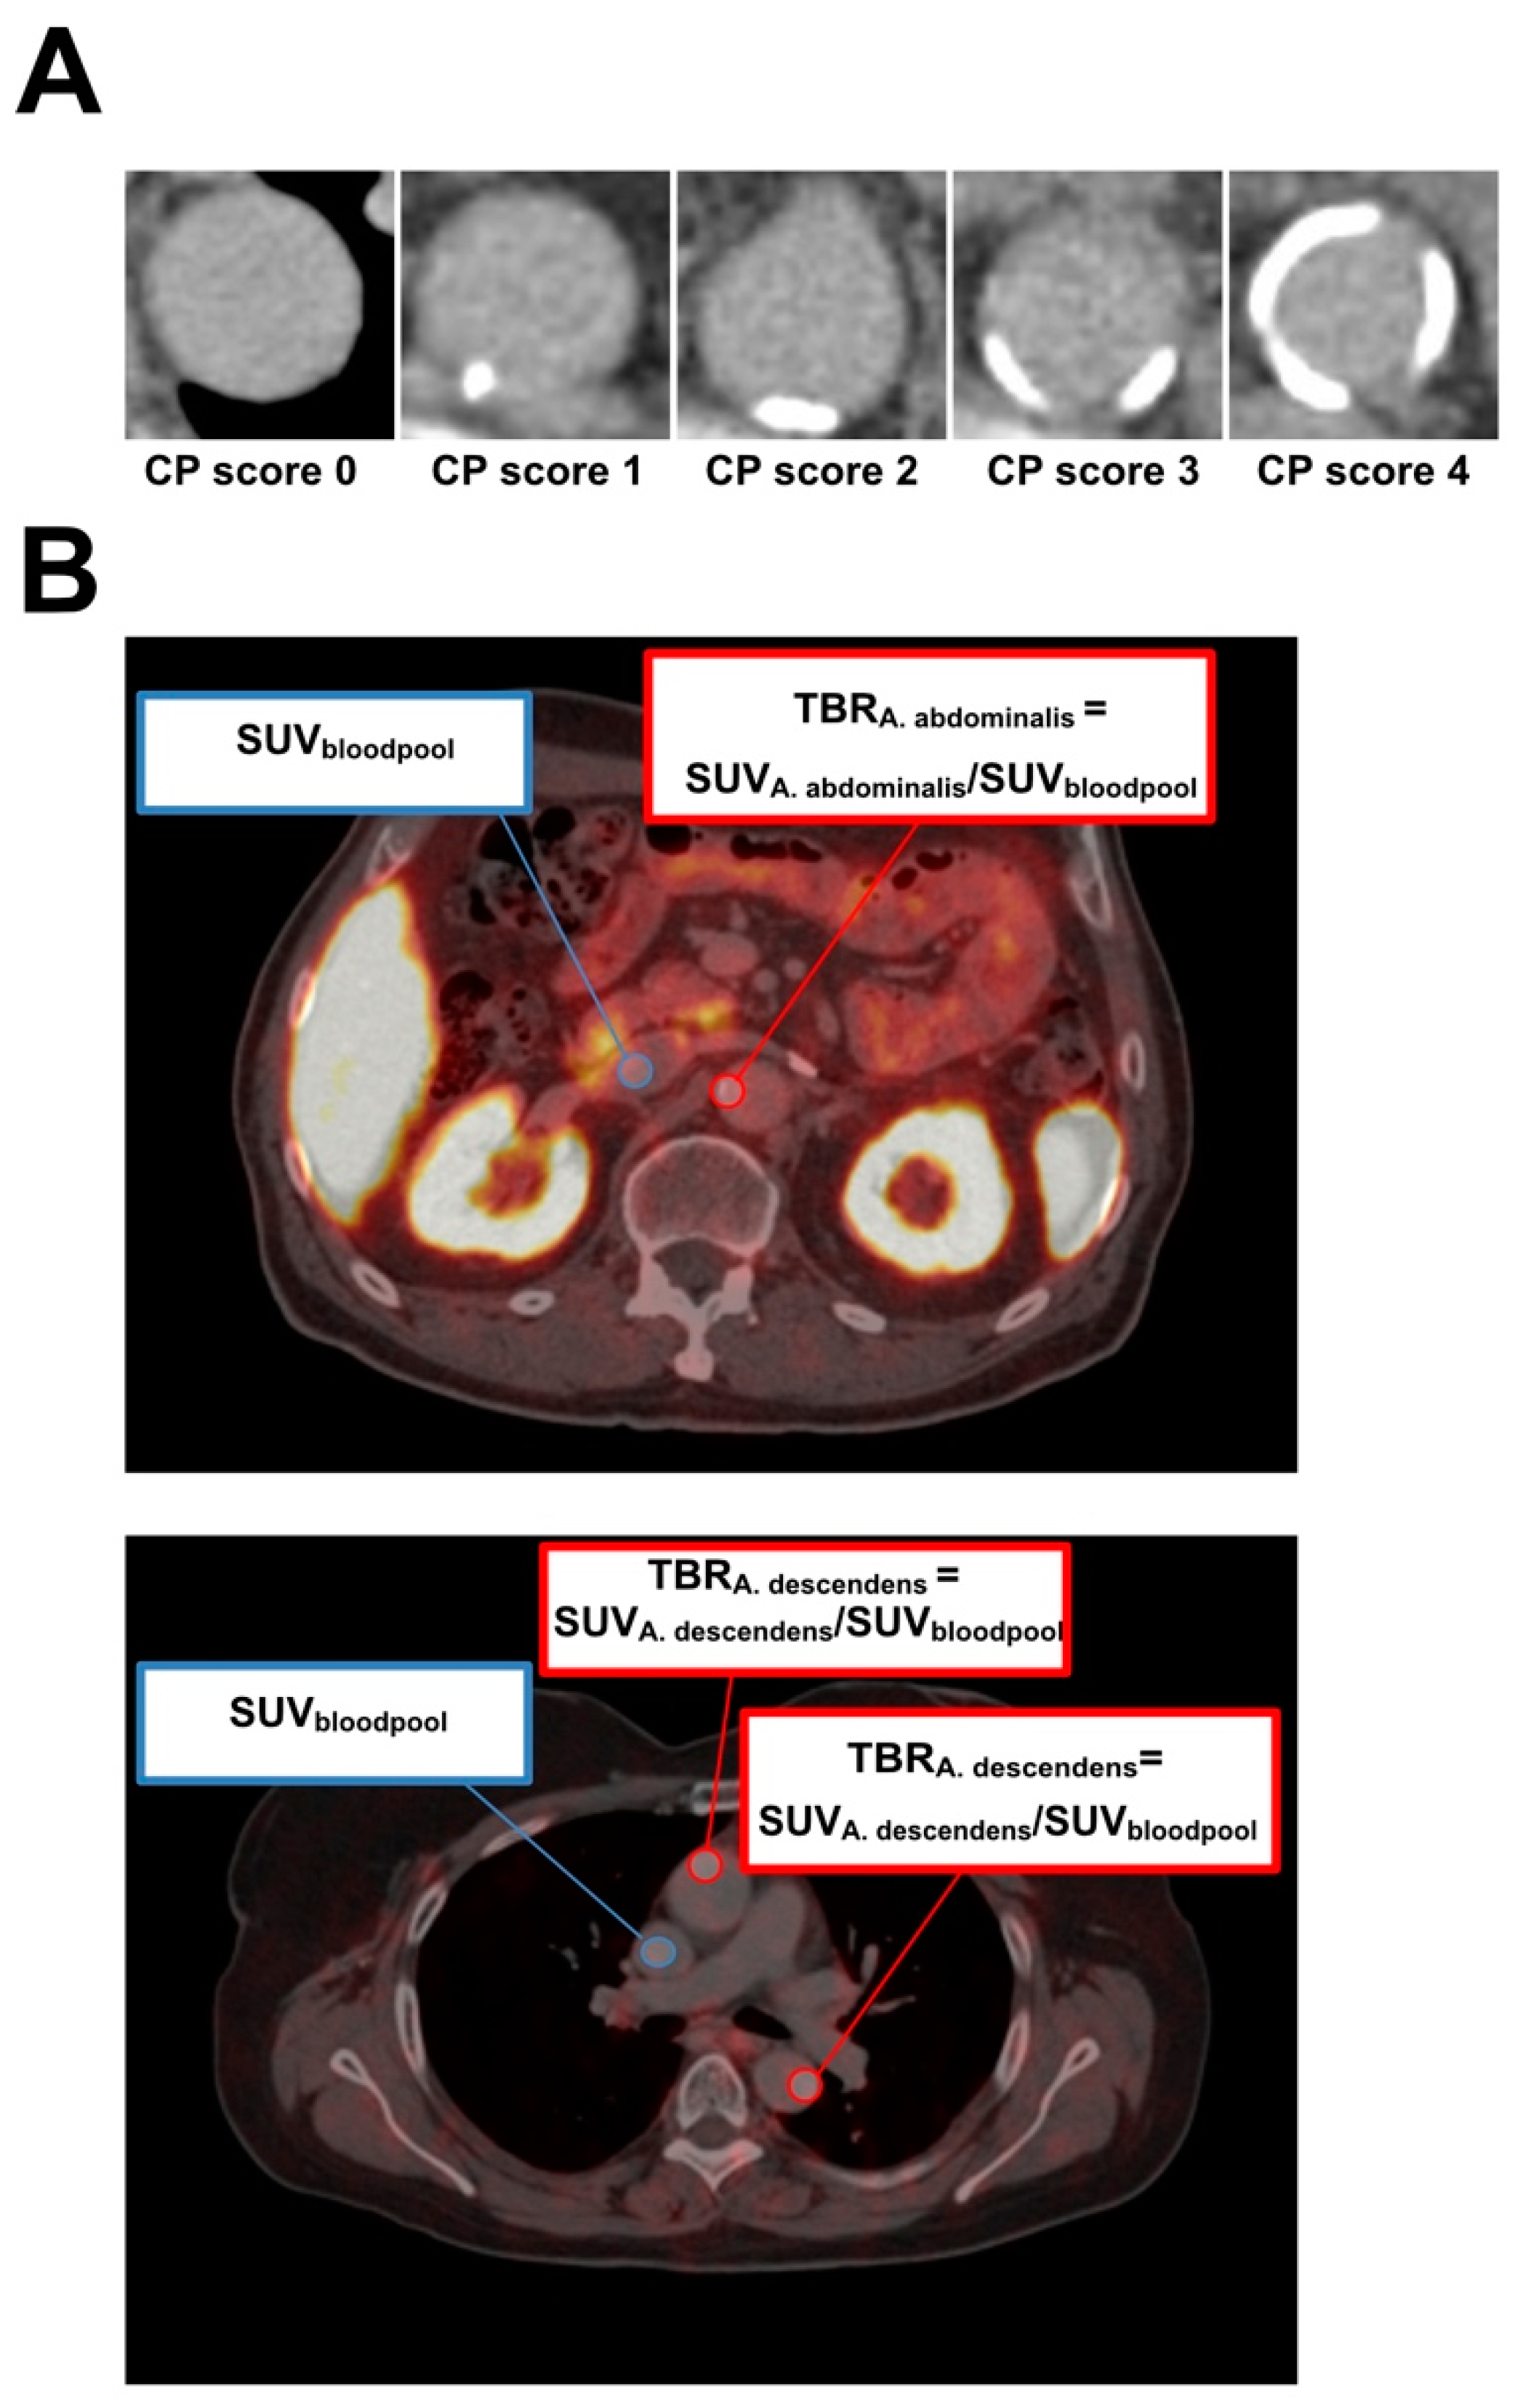

2.3. Image Analysis

3.2. Correlation of Calcified Plaque Score, Overall Vessel Uptake (OVU), and Age

3.3. Correlation of Each Vessel Segment to OVU